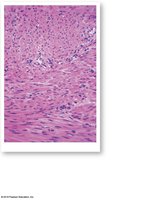

Smooth Muscle Tissue

Structure and Function

Found in walls of hollow organs, blood vessels, and other systems.

Spindle-shaped cells, single central nucleus, nonstriated.

No T tubules or sarcomeres; thin filaments attached to dense bodies.